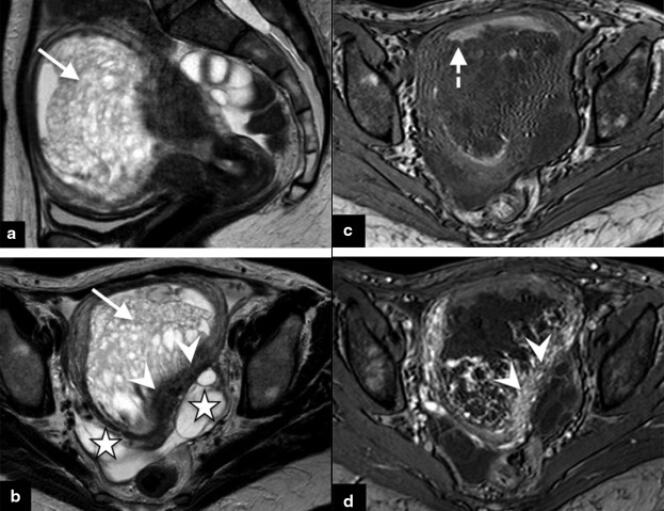

IRM pelvienne mettant en évidence une môle invasive chez une patiente de 40 ans présentant des hémorragies de l’utérus. PIERRE-ADRIEN BOLZE Ce sont des tumeurs féminines méconnues,d’autant plus cruelles qu’elles surviennent à l’occasion de l’attente d’un « heureux événement ». Chez près d’une femme enceinte sur mille en Occident (et près d’une sur cent en Asie),en effet,une masse tumorale se développe à partir du placenta,cet organe essentiel qui assure les échanges entre le sang de la mère et celui de l’embryon.